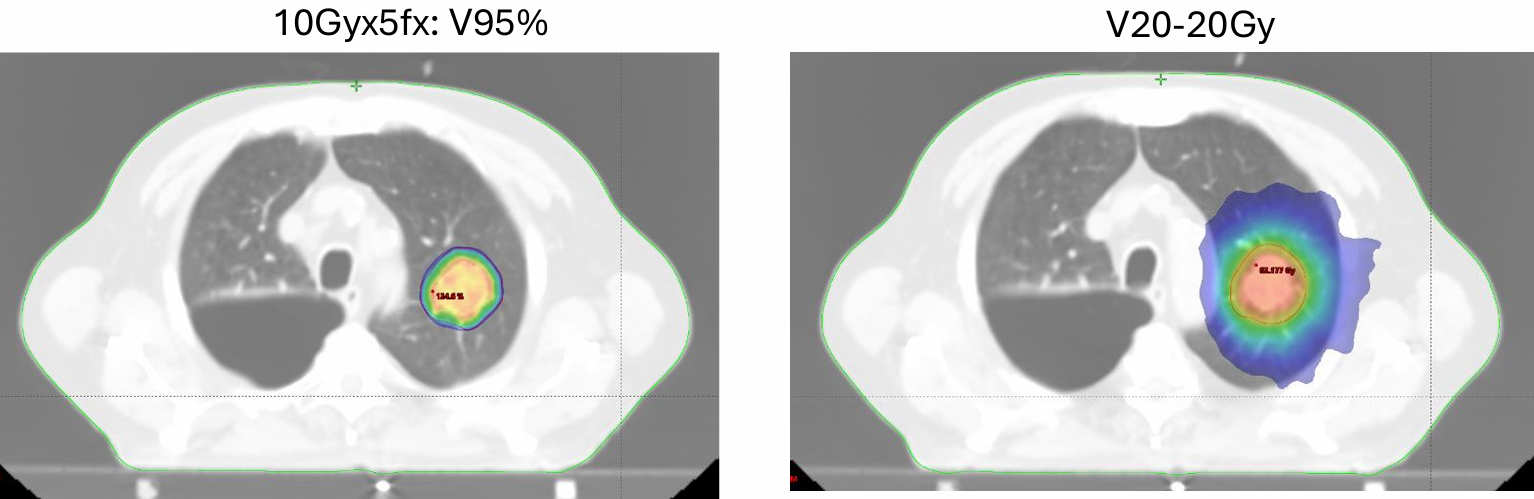

治疗技术采用每日图像引导(IGRT)的SBRT,处方剂量为总剂量50Gy,分割方式为每次10Gy,共5次,每日1次。